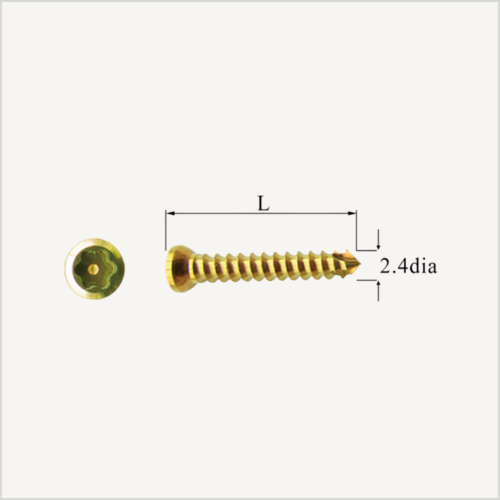

Implante PRCL Mini de 4 mm de ancho, 89.5 mm de longitud y 20 agujeros para el sistema PRCL Mini, diseñado para ofrecer una estabilización eficaz en procedimientos de cirugía ortopédica veterinaria.

Su diseño favorece una adaptación anatómica adecuada y una correcta distribución de cargas. Fabricado en material biocompatible, proporciona un rendimiento fiable y duradero en pacientes de pequeño tamaño.